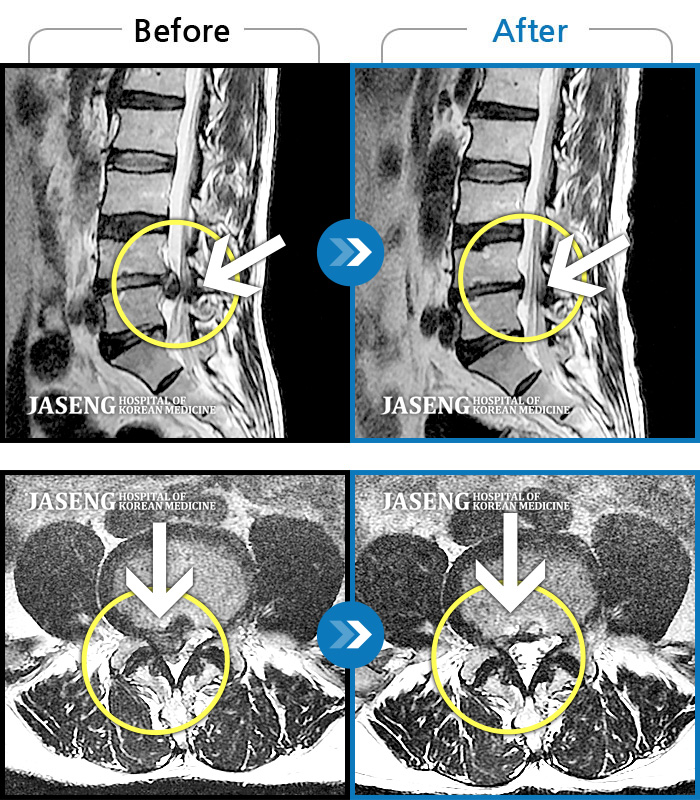

허리디스크

일산 · 김태용 원장

허리 골반통증이 극심했다.

촬영시기

2021.02.06 ~ 0222.01.15

2022.01.17